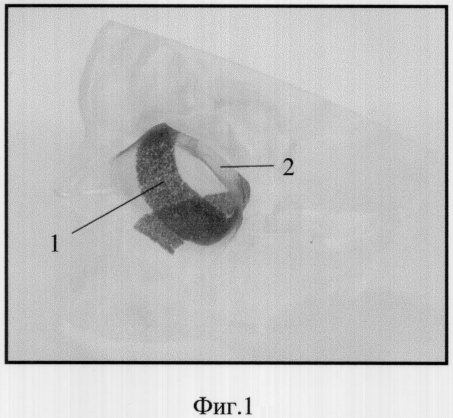

Фиг.1. Внешний вид имплантата для реконструктивной пластики обширных дефектов на макете лицевого скелета. 1 – фрагменты опорного каркаса, 2 – поддерживающая сетка.

Больному проведена операция с использованием имплантата из никелида титана предлагаемой конструкции. Он содержит опорный каркас в виде пластины (1 фиг.1) из пористого никелида титана толщиной 0,5 мм, шириной 5 мм, дугообразно изогнутой по кривизне глазницы, и сетку из проволоки диаметра 50 мкм, сплетенную по текстильной технологии (3 фиг.4) с размером ячейки 500 мкм. Устройство по ходу операции используется и действует следующим образом:

Поддерживающая проволочная сетка 2 подведена под мобилизованный глаз и его вспомогательные органы. Края сетки зафиксированы ущемлением их в маргинальных тканях. Опорный каркас 1 (фиг.1) продвижением в краниальном направлении подведен к комплексу сетка-орган и зафиксирован на краях костного дефекта простым наложением без вспомогательных крепежных средств. Таким образом, пролабированный комплекс сетка-орган оперся на опорный каркас на некоторой площади пятна соприкосновения (фиг.3). Оставшаяся после удаления блока (фиг.2) полость заполнена йодоформным тампоном. Операция завершена установкой защитной пластмассовой пластины, отграничивающей полость рта от послеоперационной полости, и ушиванием раны.

Сходство техники и результатов обоих примеров конкретных операций, выполненных в различных участках организма, дает основание, по компетентному мнению осведомленных хирургов, предположить широкую область применения предлагаемого имплантата и обоснованность заявленной общности. Вариации структурного состава имплантата в рамках таковой тогда должны соответствовать специфике конкретных показаний (например, наличие двух или более элементов опорного каркаса, как представлено на фиг.1).